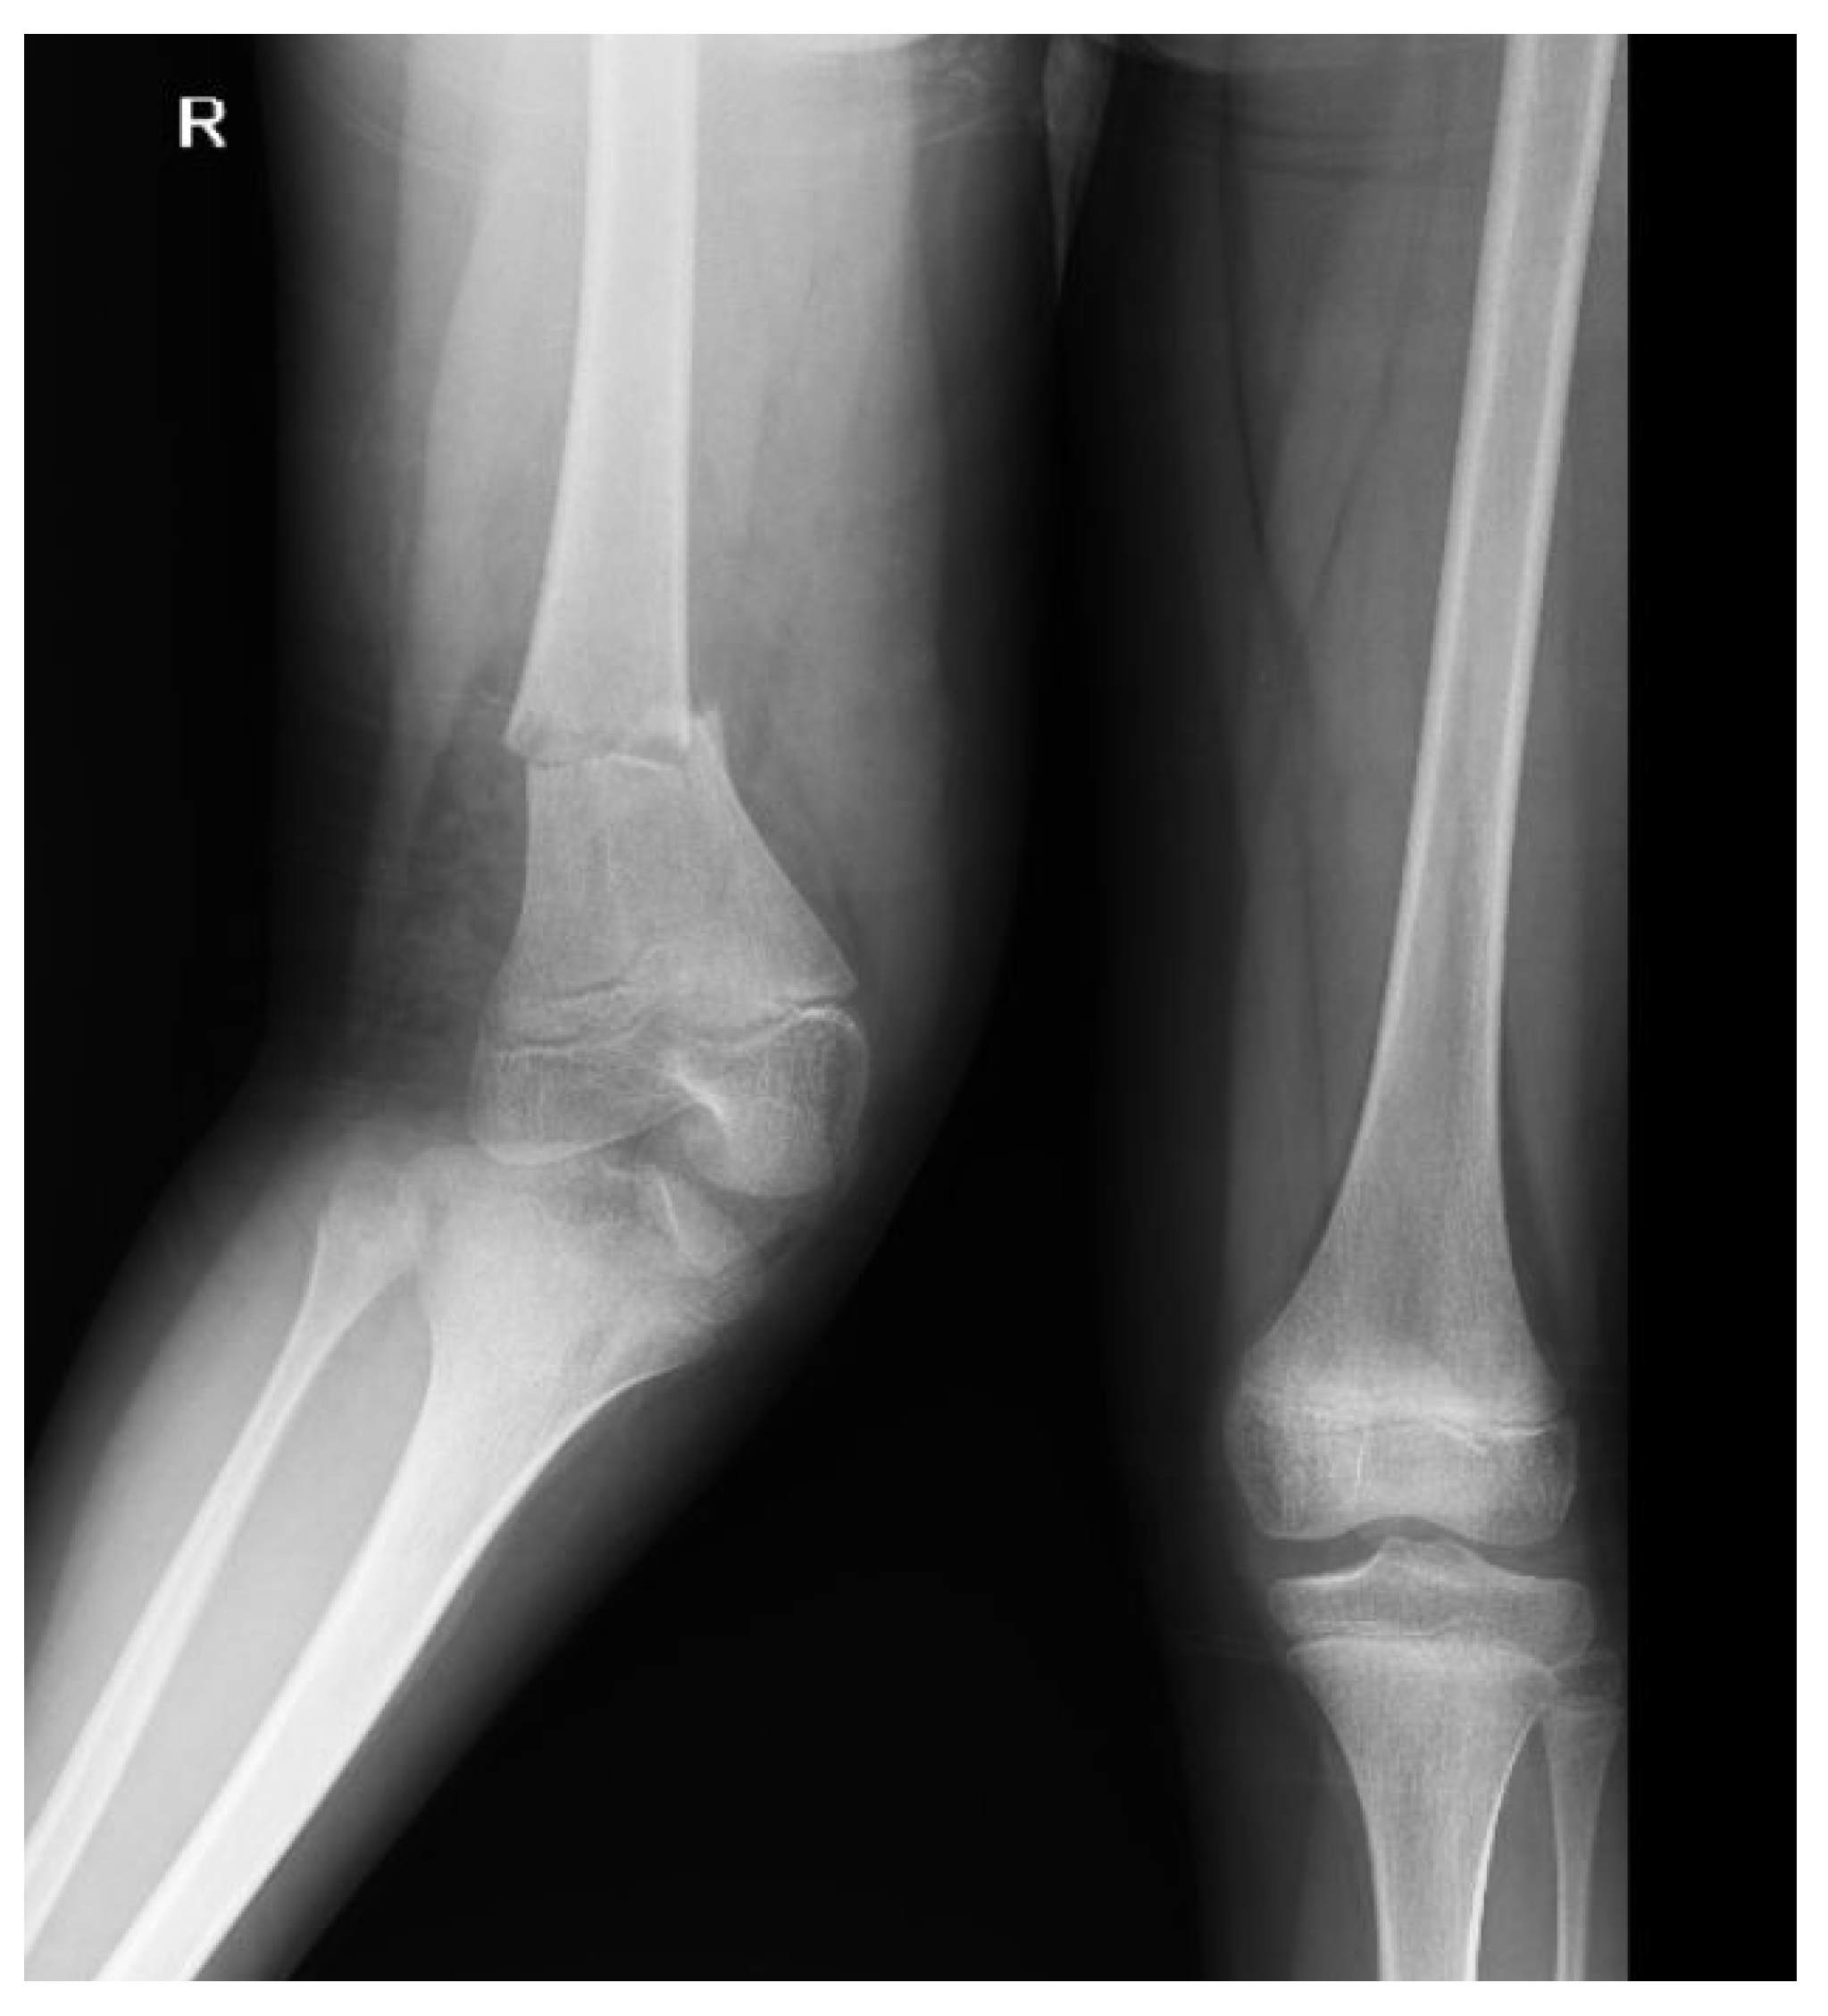

| Limb | 5 (26.3) | 14 (73.7) | 41 (29.1) | 100 (70.9) | 46 (28.7) | 114 (71.3) | 0.803 |